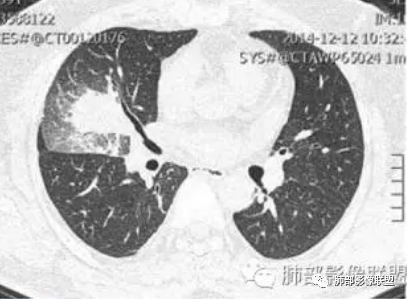

这三个月后的

大雄:

我只是要告诉大家,不是二元,就是肿瘤,没有什么感染,磨玻璃都没消失。